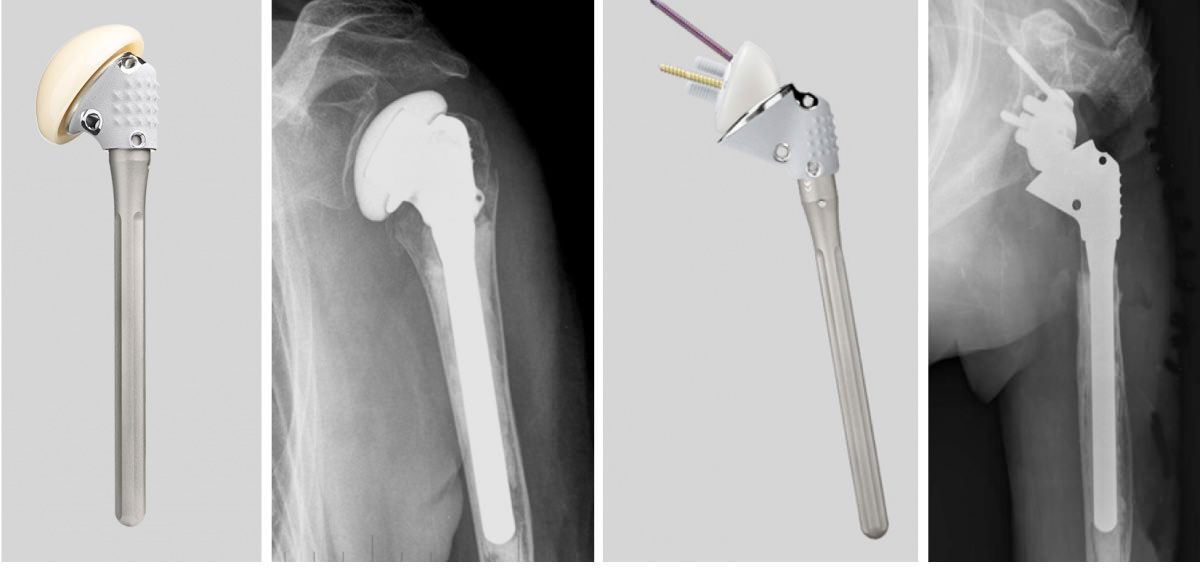

Grundsätzlich wird zwischen anatomischen und inversen Schulterendoprothesen unterschieden. Während anatomische Prothesen (vor allem Oberflächenersatz-, Kurzschaft- und Schaftprothesen) die zerstörten Gelenkoberflächen ersetzen (wie dies z.B. bei der Arthrose der Fall ist) und die ursprüngliche Geometrie des Gelenkes wieder herstellen sollen (Abb. 1), stellen inverse Endoprothesen die natürlichen Verhältnisse „auf den Kopf“. Sie kommen zum Einsatz, wenn nicht nur die Gelenkkörper selbst verändert sind, sondern zusätzlich massive Schäden an den Weichteilen, vor allem an der sogenannten Rotatorenmanschette vorliegen. Durch Befestigung eines festen Widerlagers am Schulterblatt wird die Stabilität des Gelenkes wieder hergestellt, sodass die verbliebene, noch funktionsfähige Muskulatur, den Arm wieder bewegen kann.

Diese Prothesen weisen besondere technische Möglichkeiten auf, um zum einen die Länge des Armes wieder herstellen zu können und zum anderen die Knochenfragmente fest an der Prothese zu fixieren, damit diese miteinander verheilen können (Abbildung a,b). Dies ist die wichtigste Voraussetzung für eine gute spätere Funktion. In zunehmendem Maße werden primär inverse Prothesen eingesetzt (Abbildung c,d).

Abbildung: Frakturprothese (Affinis fracture): a) Auf dem zementierbaren Schaft ist im oberen Teil ein verschiebbares Zwischenstück zum Längen- und Rotationsausgleich montiert. Zur Unterstützung der knöchernen Einheilung wurde die Oberfläche speziell beschichtet; b) Im Röntgenbild ist die sorgfältige Anlagerung der knöchernen Fragmente im oberen Abschnitt gut zu erkennen. c,d) Auch bei den inversen Frakturprothesen besitzt der Prothesenschaft spezielle Komponenten zur Anpassung der Prothese.

Dieser Prothesentyp kommt meist zum Einsatz, wenn eine Defektarthropathie vorliegt, also eine Kombination aus degenerativen Gelenkveränderungen und nicht reparablem Rotatorenmanschettendefekt (Abb. 2).

Hierbei handelt es sich um eine relativ häufige Erkrankung. Inverse Prothesen eignen sich aber auch für schwere Defektzustände nach fehlverheilten Frakturen, für Wechseloperationen bei Prothesenlockerung, nach Versagen einer anatomischen Frakturprothese, bei Tumoren und anderen Krankheitsbildern, d.h. sie sind immer dann angezeigt, wenn neben den Gelenkkörpern auch schwere Muskel und Sehnenschäden vorliegen. Spezielle, verstellbare inverse Frakturprothesen erleichtern in diesen Fällen die Anpassung an die pathologischen Bedingungen (Abb. 2).

Abb. 2: a) Schwere Rotatorendefektarthropathie mit Zerstörung des Kopfes, der Pfanne und auch des Gleitraumes unter dem Schulterdach als Folge eines irreparablen Rotatorenmanschettendefektes; b) Zementfrei implantierte inverse Schulterprothese (Delta-X-tend); c) Zementiert implantierte inverse Endoprothese (Affinis inverse); d) Bei der letztgenannten Prothese besteht die kugelförmige Komponente aus Polyäthylen (mit dem Ziel einer längeren Haltbarkeit der Prothese), so dass sie im Röntgenbild nicht sichtbar ist.